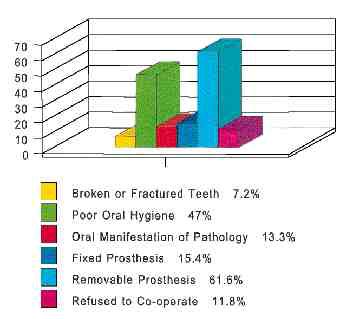

ABSTRACT: In 1994, the Dental Clinic was created at the Queensway Carleton Hospital (QCH), through the generous donation of Dr. M Lorne E. Macalchlan , a long-term care patient. The fund was earmarked for use in regards to elderly patients at the institution. The hospital itself is a 201-bed facility located in Nepean, Ontario, Canada … Read more